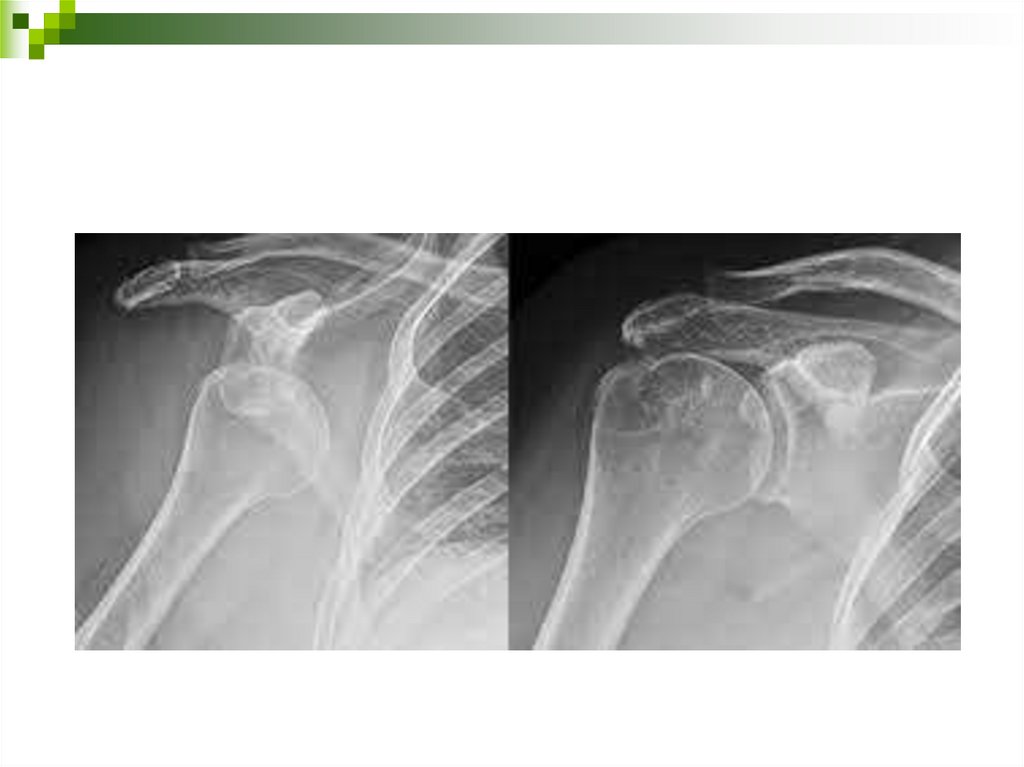

9.

10.

11. Диагностика вывихов

Клинические признаки:

- боль;

- деформация сустава;

- изменение внешних ориентиров сустава;

- отсутствие активных движений в суставе;

- при пассивных движениях симптом пружинящего

сопротивления (ощущение упругого сопротивления

движению, а при прекращении усилия сегмент

конечности возвращается в прежнее положение)

- при пальпации головка кости пальпируется в не типичном

месте.